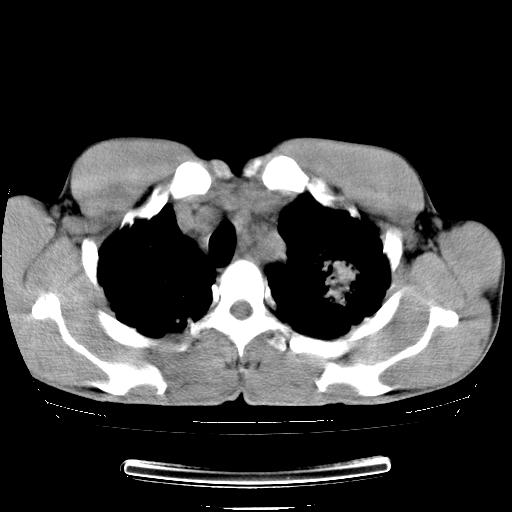

以下是引用yangyudong333在2008-4-29 5:38:00的发言:[br]比较典型的矽肺结节.支持[br]诊断依据:[br] 1.x线表现:[br] ①典型矽肺为多发直径 1~3mm 小结节,即矽结节,由胶原纤维和硅尘构成,可融合成团块,好发于上肺。[br] ②团块周围常有肺大泡。[br] ③胸内淋巴结增大、钙化。如肺门淋巴结呈蛋壳样钙化有助于与其他尘肺区别。[br] ④胸膜常广泛粘连、增厚。[br] 2.ct表现[br] ①两肺散在大小较为一致的小结节影,其密度较高,边界清楚。[br] ②小结节可融合为较大团块影,直径约 1cm ,甚至可达 10cm以上,易发生在上叶。[br] ③小结节周围常并有小叶中心气肿或弥漫性肺气肿。

以下是引用liuyue在2008-4-28 22:30:00的发言:[br]比较典型的矽肺结节.[br]请结合临床及化验除外矽肺合并肺结核之可能.